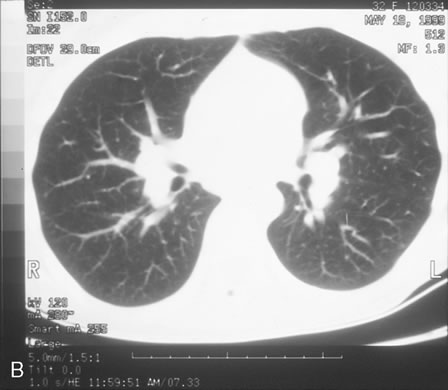

Pneumocystis carinii pneumonia once was the most common presentation of AIDS. It is typically of insidious onset, with features including dry cough, dyspnea, and a diffuse bilateral interstitial infiltrate evident on a chest roentgenogram. Typical multifocal fundus lesions have been described. They are yellow-white and have a characteristic pattern on fluorescein angiography (Fig. 10A, 10B, and 10C). Diagnosis is made by demonstrating the protozoon via sputum induction, bronchioalveolar lavage, and transbronchial or open-lung biopsies. Treatment modalities include trimethoprim-sulfamethoxazole (TMP-SMX).31